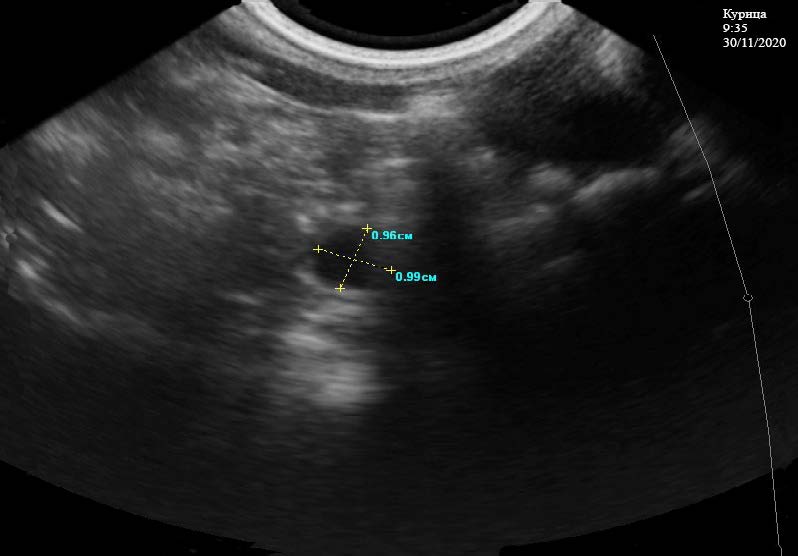

При ультразвуковом исследовании почек у курицы отмечается, что их границы ровные, четкие. Эхоструктура кортикального и мозгового слоев в срединной плоскости неоднородная, эхогенность паренхимы соответствует норме. Капсула не визуализируется. Отчетливо видно наличие более светлых и темных участков в паренхиме, что связано с фильтрацией минеральных веществ, содержащихся в крови. Мочеточники на всем протяжении не визуализируются. Общая длина почек составляет 4,70 см (рис. 1). Ультразвуковое исследование половых органов у курицы кросса Хайсекс белый проводилось в несколько этапов: Начало первого этапа проводили в 9:35 часов 30.11.2020 г. Отмечено наличие созревшего фолликула, который попадает в воронку. Выявляются локализованные объемные образования округлой формы – фолликулы, находящиеся на разных стадиях развития, размерами 0,96*0,99, 1,82*1,97, 0,57*0,70 см (рис. 2). Они имеют однородную эхогенность и эхоструктуру гиперэхоогенного характера, дающие слабую акустическую тень. Вокруг них визуализируется несколько мелких фолликулов, состояние границ между ними четкое просматривается, наличия артефактов не отмечено.

Рис. 2. Фолликулы на разных стадий развития в яичнике у курицы кросс «Хайсекс белый». 9:35 ч. 30.11.2020 г.